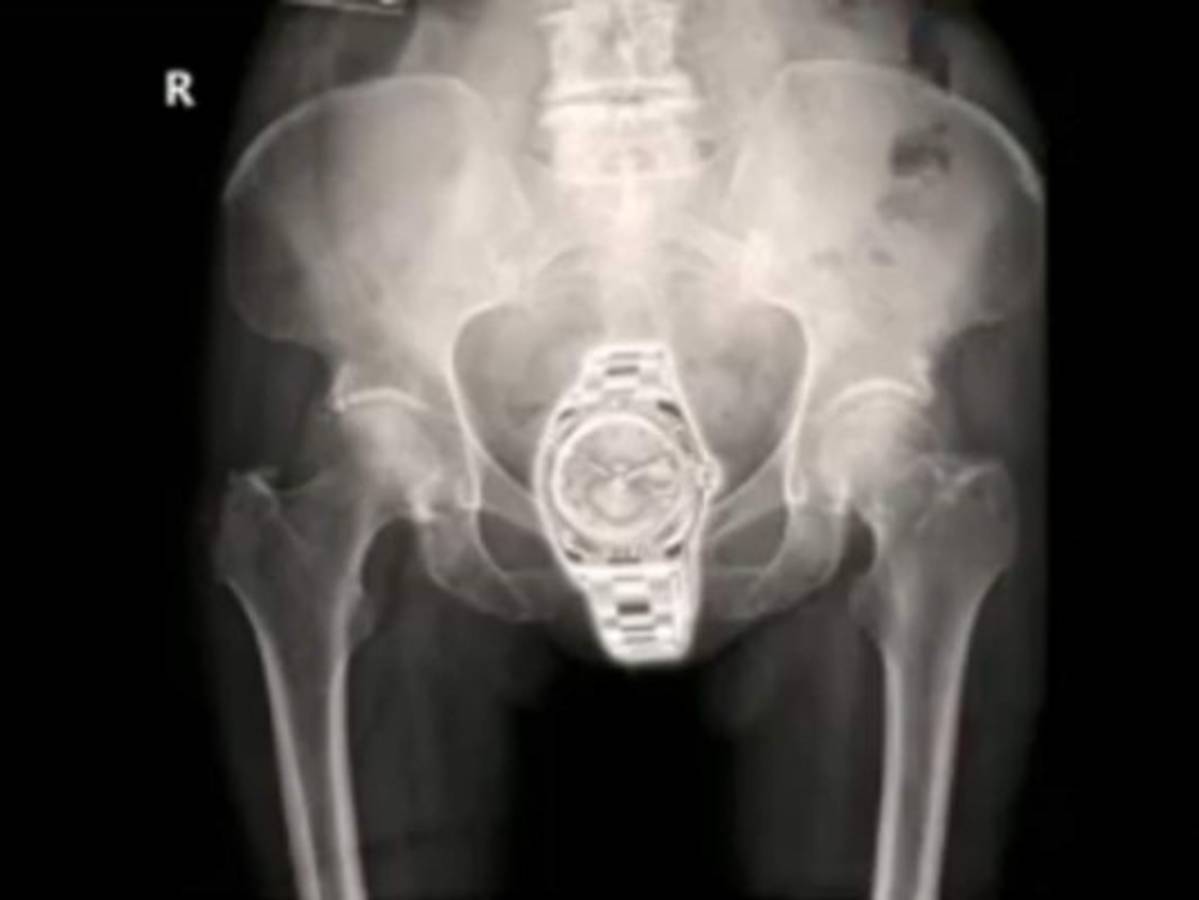

La mujer fue trasladada por las autoridades a un hospital donde le realizaron radiografías y descubrieron que el reloj lo llevaba escondido dentro de su vagina. A Lafave se le fijó una fianza de $40,000 y podría enfrentar hasta 20 años de prisión de ser encontrada culpable.